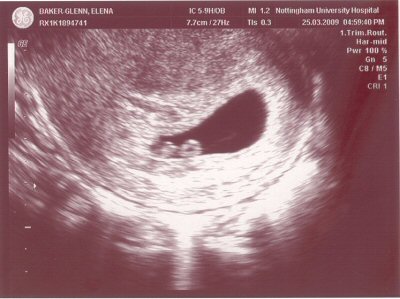

- The scan photo shown below is the dating scan. The due date is 8th November 2009, meaning that the baby was 12 + 2 weeks gestation at the time of the scan. The CRL was 57mm.